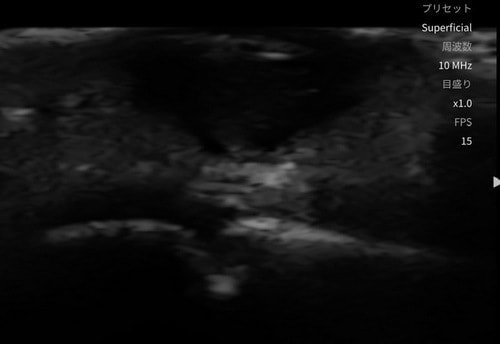

分厚いタコがあり皮膚の下を触診で診察しにくいため、エコー検査をしてみました。粉瘤の診断になりました。

足底粉瘤の術前エコー